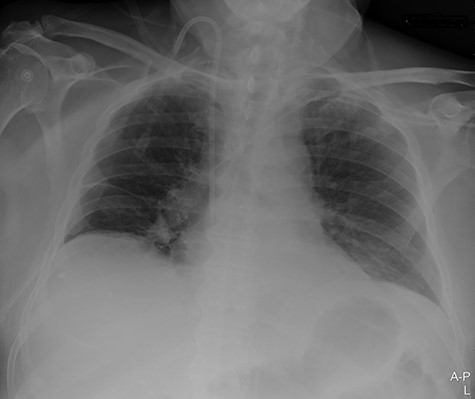

A 74-year-old male patient with a history of type 2 diabetes mellitus, ankylosing spondylitis and cystoprostatectomy with Bricker bladder was admitted with acute renal failure not responding to conservative measures. He needed haemodialysis. Due to clinical deterioration with dyspnoea, hypotension and inadequate peripheral perfusion during intermittent haemodialysis, he was transferred to the intensive care unit (ICU). A right-sided pleural effusion was found, and the intensivist inserted a pigtail pleural drain under ultrasound guidance. The fluid was somewhat bloody, but control with ultrasound and CXR (Fig. 1) after the procedure was normal.

Portable chest X-ray with no pleural effusion after placement of pigtail pleural drain.